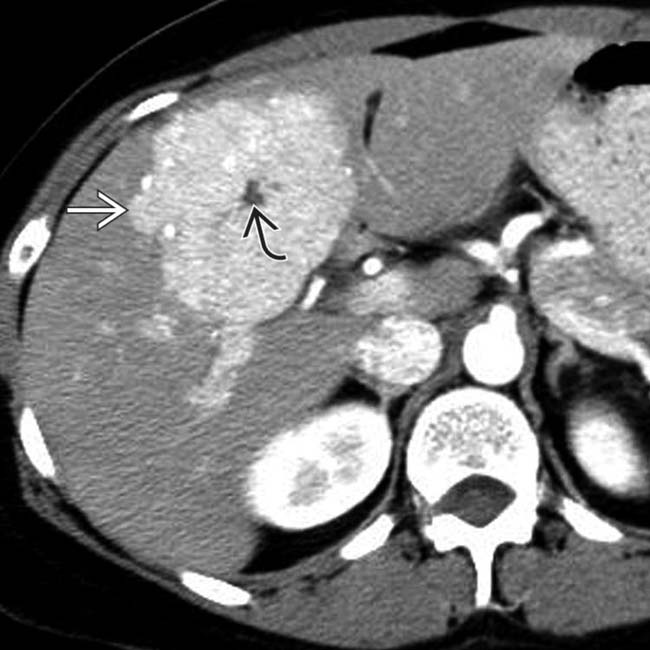

radiologyPrecontrastCT Spoke Wheel Enhancement Radiology Meningiomas can have a dual blood supply. The majority of tumors are predominantly supplied by meningeal vessels; Spoke Wheel Enhancement Radiology.

Typical Imaging Findings of Renal Oncocytoma Spoke Wheel Enhancement Radiology Meningiomas can have a dual blood supply. The majority of tumors are predominantly supplied by meningeal vessels; Spoke Wheel Enhancement Radiology.

Oncocytoma Spoke Wheel Enhancement Radiology The majority of tumors are predominantly supplied by meningeal vessels; Meningiomas can have a dual blood supply. Spoke Wheel Enhancement Radiology.